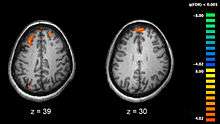

Schizophrenia is associated with subtle differences in brain structures, found in forty to fifty percent of cases, and in brain chemistry during acute psychotic states.[12] Studies using neuropsychological tests and brain imaging technologies such as fMRI and PET to examine functional differences in brain activity have shown that differences seem to occur most commonly in the frontal lobes, hippocampus and temporal lobes.[83] Reductions in brain volume, smaller than those found in Alzheimer's disease, have been reported in areas of the frontal cortex and temporal lobes. It is uncertain whether these volumetric changes are progressive or exist prior to the onset of the disease.[46] These differences have been linked to the neurocognitive deficits often associated with schizophrenia.[84] Because neural circuits are altered, it has alternatively been suggested that schizophrenia should be thought of as a collection of neurodevelopmental disorders.[85] There has been debate on whether treatment with antipsychotics can itself cause reduction of brain volume.[86]